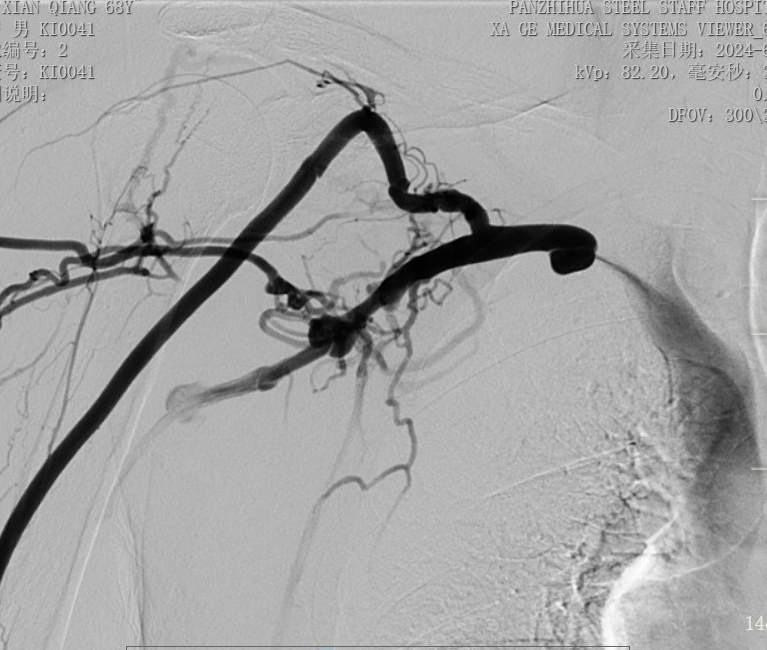

術(shù)前造影顯示右鎖骨下靜脈幾乎閉塞

手術(shù)中,主刀醫(yī)生唐靜通過DSA順利對人工血管中形成的血栓進(jìn)行了取栓。之后,在中心靜脈造影下,發(fā)現(xiàn)患者中心靜脈外周有2cm的狹窄,尤其是右鎖骨下靜脈得狹窄已經(jīng)嚴(yán)重到幾乎閉塞,針眼大小的縫隙僅能容下導(dǎo)絲通過。經(jīng)過反復(fù)嘗試與不懈努力,終于將導(dǎo)絲置入,并用12 *40mm的球囊擴(kuò)張,右鎖骨下靜脈成功開通,患者透析的通道打開了。術(shù)后,家屬看著消腫的手臂感激萬分,眼淚奪眶而出。